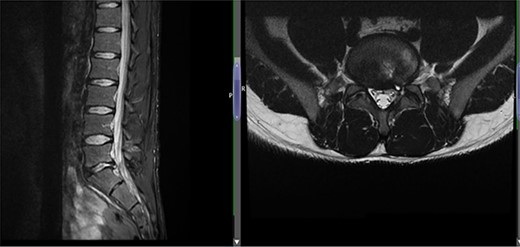

(A) Case 2—initial MRI shows a slightly unusual abnormality associated with the L5-S1 compressing the left transiting S1 nerve root and is almost certainly a fragment of extruded/sequestered disc, and (B) case 2—updated MRI shows a significant decrease in the previously seen cystic lesion at L5-S1 level now measuring 4 mm (AP diameter, previously 11 mm).